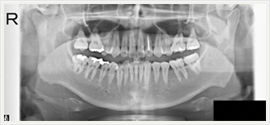

画像紹介

その他